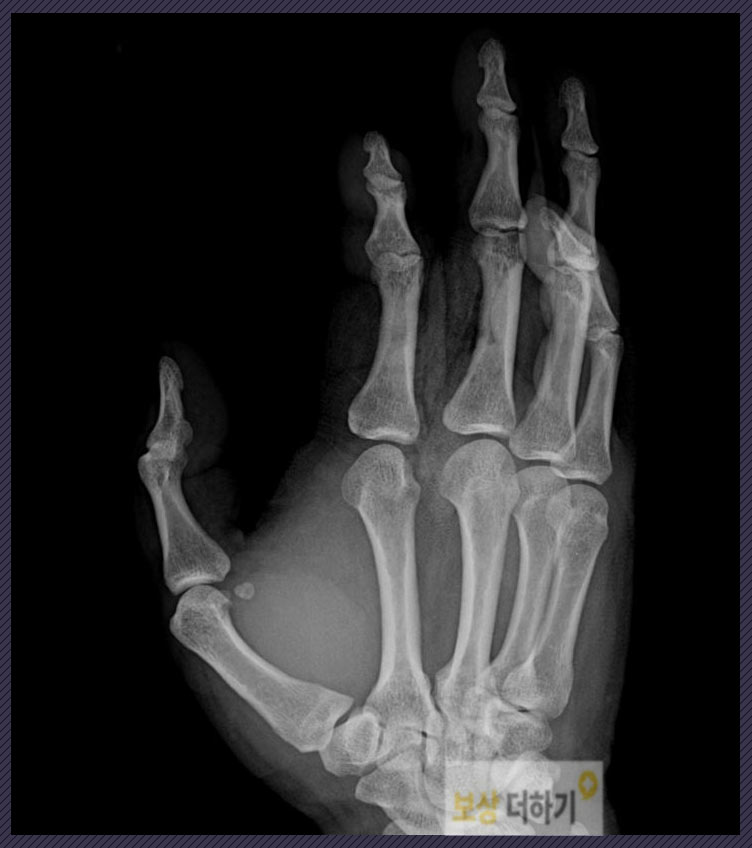

진단: S62631, S6610, S610, T888 우측 2,3,4수지 즉 오른쪽 검지, 중지, 약지 손가락 모두 부상을 입었는데요. 피부연부조직 결손 및 2수지 골절, 3수지 굴곡건 즉 인대파열 4수지 피부 괴사 등의 진단을 받았습니다.

이로 인해 수술적 치료가 필요했습니다. 골절된 손가락 뼈는 제 위치를 잘 맞추어 고정을 시켜줘야 했기에 내고정술을 하였고, 굴곡건 파열 즉 인대가 파열된 부분은 건봉합술을 시행하였습니다. 그 외에 연부조직 결손에 대한 치료도 포함하여 모든 수술을 무사히 마쳤습니다.